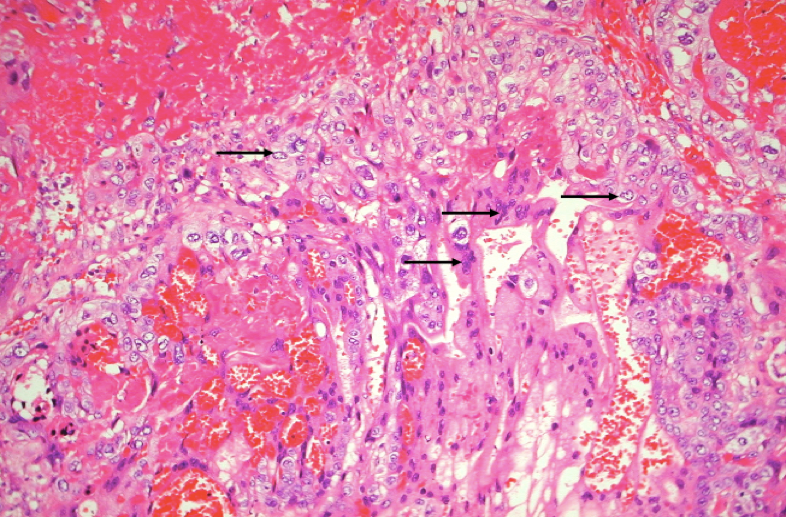

(2)镜下,瘤组织由分化不良的细胞滋养层和合体细胞滋养层两种瘤细胞组成,细胞异型性明显,核分裂像易见。两种细胞混合排列成巢状或条索状,偶见个别癌巢主要由一种细胞组成。肿瘤自身无间质血管,依靠侵袭宿主血管获取营养,故癌组织和周围正常组织有明显出血坏死,有时癌细胞大多坏死,仅在边缘部查见少数残存的癌细胞。癌细胞不形成绒毛和水泡状结构,这一点和侵蚀性葡萄胎明显不同。

细胞滋养层细胞(郎罕细胞)位于正常绒毛内层,呈立方或多边形,胞浆淡染,核圆居中,染色质较稀疏。合体滋养层细胞位于正常绒毛的外层,细胞体积大而不规则,胞浆嗜酸呈深红色,多核,核深染而不规则。正常绒毛在妊娠3个月后,滋养层细胞仅剩合体滋养层细胞,而葡萄胎时这两种细胞皆持续存在,并活跃增生,失去正常排列,呈多层或成片聚集。